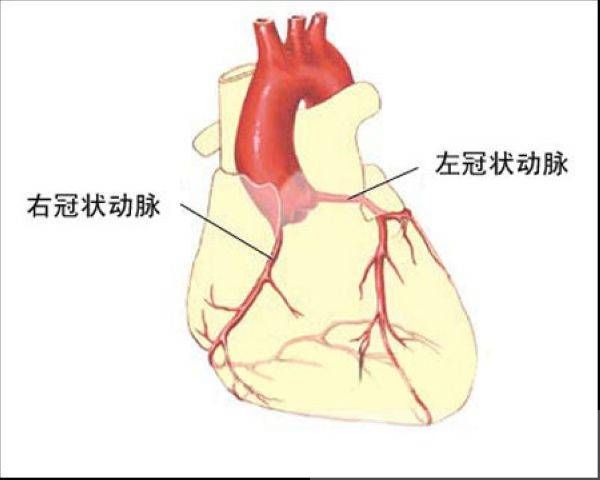

肺源性心脏病(简称肺心病)主要是由于支气管-肺组织或肺动脉血管病变所致肺动脉高压引起的心脏病。根据起病缓急和病程长短,可分为急性和慢性两类。临床上以后者多见。本病发展缓慢,临床上除原有肺、胸疾病的各种症状和体征外,主要是逐步出现肺、心功能衰竭以及其他器官损害的征象。

慢性肺源性心脏病是由于慢性支气管、肺、胸廓或肺动脉血管慢性病变所致的肺循环阻力增加、肺动脉高压、进而使右心肥厚、扩大,伴或不伴右心功能衰竭的心脏病。急性肺源性心脏病主要是由肺动脉主干或其主要分支突然栓塞,肺循环大部受阻,以致肺动脉压急剧增高、急性右心室扩张和右心室功能衰竭的心脏病。按其功能的代偿期与失代偿期进行分述。

此期主要是慢性阻塞性肺疾病(简称慢阻肺)的表现。慢性咳嗽、咳痰、气急,活动后心悸、呼吸困难、乏力和劳动耐力下降。体检可有明显肺气肿征,听诊呼吸音减弱,偶有干、湿性啰音,下肢轻微水肿,下午明显,次晨消失。心浊音界常因肺气肿而不易叩出。心音遥远,但肺动脉瓣区可有第二心音亢进,提示有肺动脉高压。三尖瓣区出现收缩期杂音或剑突下示心脏搏动,多提示有右心肥厚、扩大。部分病例因肺气肿使胸膜腔内压升高,阻碍腔静脉回流,可见颈静脉充盈。又因膈下降,使肝上界及下缘明显地下移。

慢性肺源性心脏病是由于慢性支气管、肺、胸廓或肺动脉血管慢性病变所致的肺循环阻力增加、肺动脉高压、进而使右心肥厚、扩大,伴或不伴右心功能衰竭的心脏病。急性肺源性心脏病主要是由肺动脉主干或其主要分支突然栓塞,肺循环大部受阻,以致肺动脉压急剧增高、急性右心室扩张和右心室功能衰竭的心脏病。按其功能的代偿期与失代偿期进行分述。

此期主要是慢性阻塞性肺疾病(简称慢阻肺)的表现。慢性咳嗽、咳痰、气急,活动后心悸、呼吸困难、乏力和劳动耐力下降。体检可有明显肺气肿征,听诊呼吸音减弱,偶有干、湿性啰音,下肢轻微水肿,下午明显,次晨消失。心浊音界常因肺气肿而不易叩出。心音遥远,但肺动脉瓣区可有第二心音亢进,提示有肺动脉高压。三尖瓣区出现收缩期杂音或剑突下示心脏搏动,多提示有右心肥厚、扩大。部分病例因肺气肿使胸膜腔内压升高,阻碍腔静脉回流,可见颈静脉充盈。又因膈下降,使肝上界及下缘明显地下移。